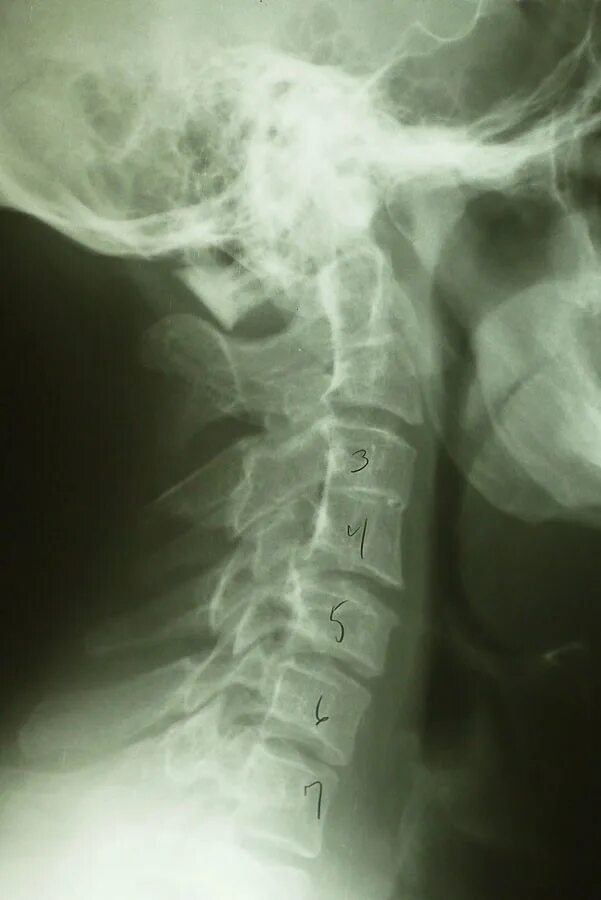

Киммерли что это такое у взрослых